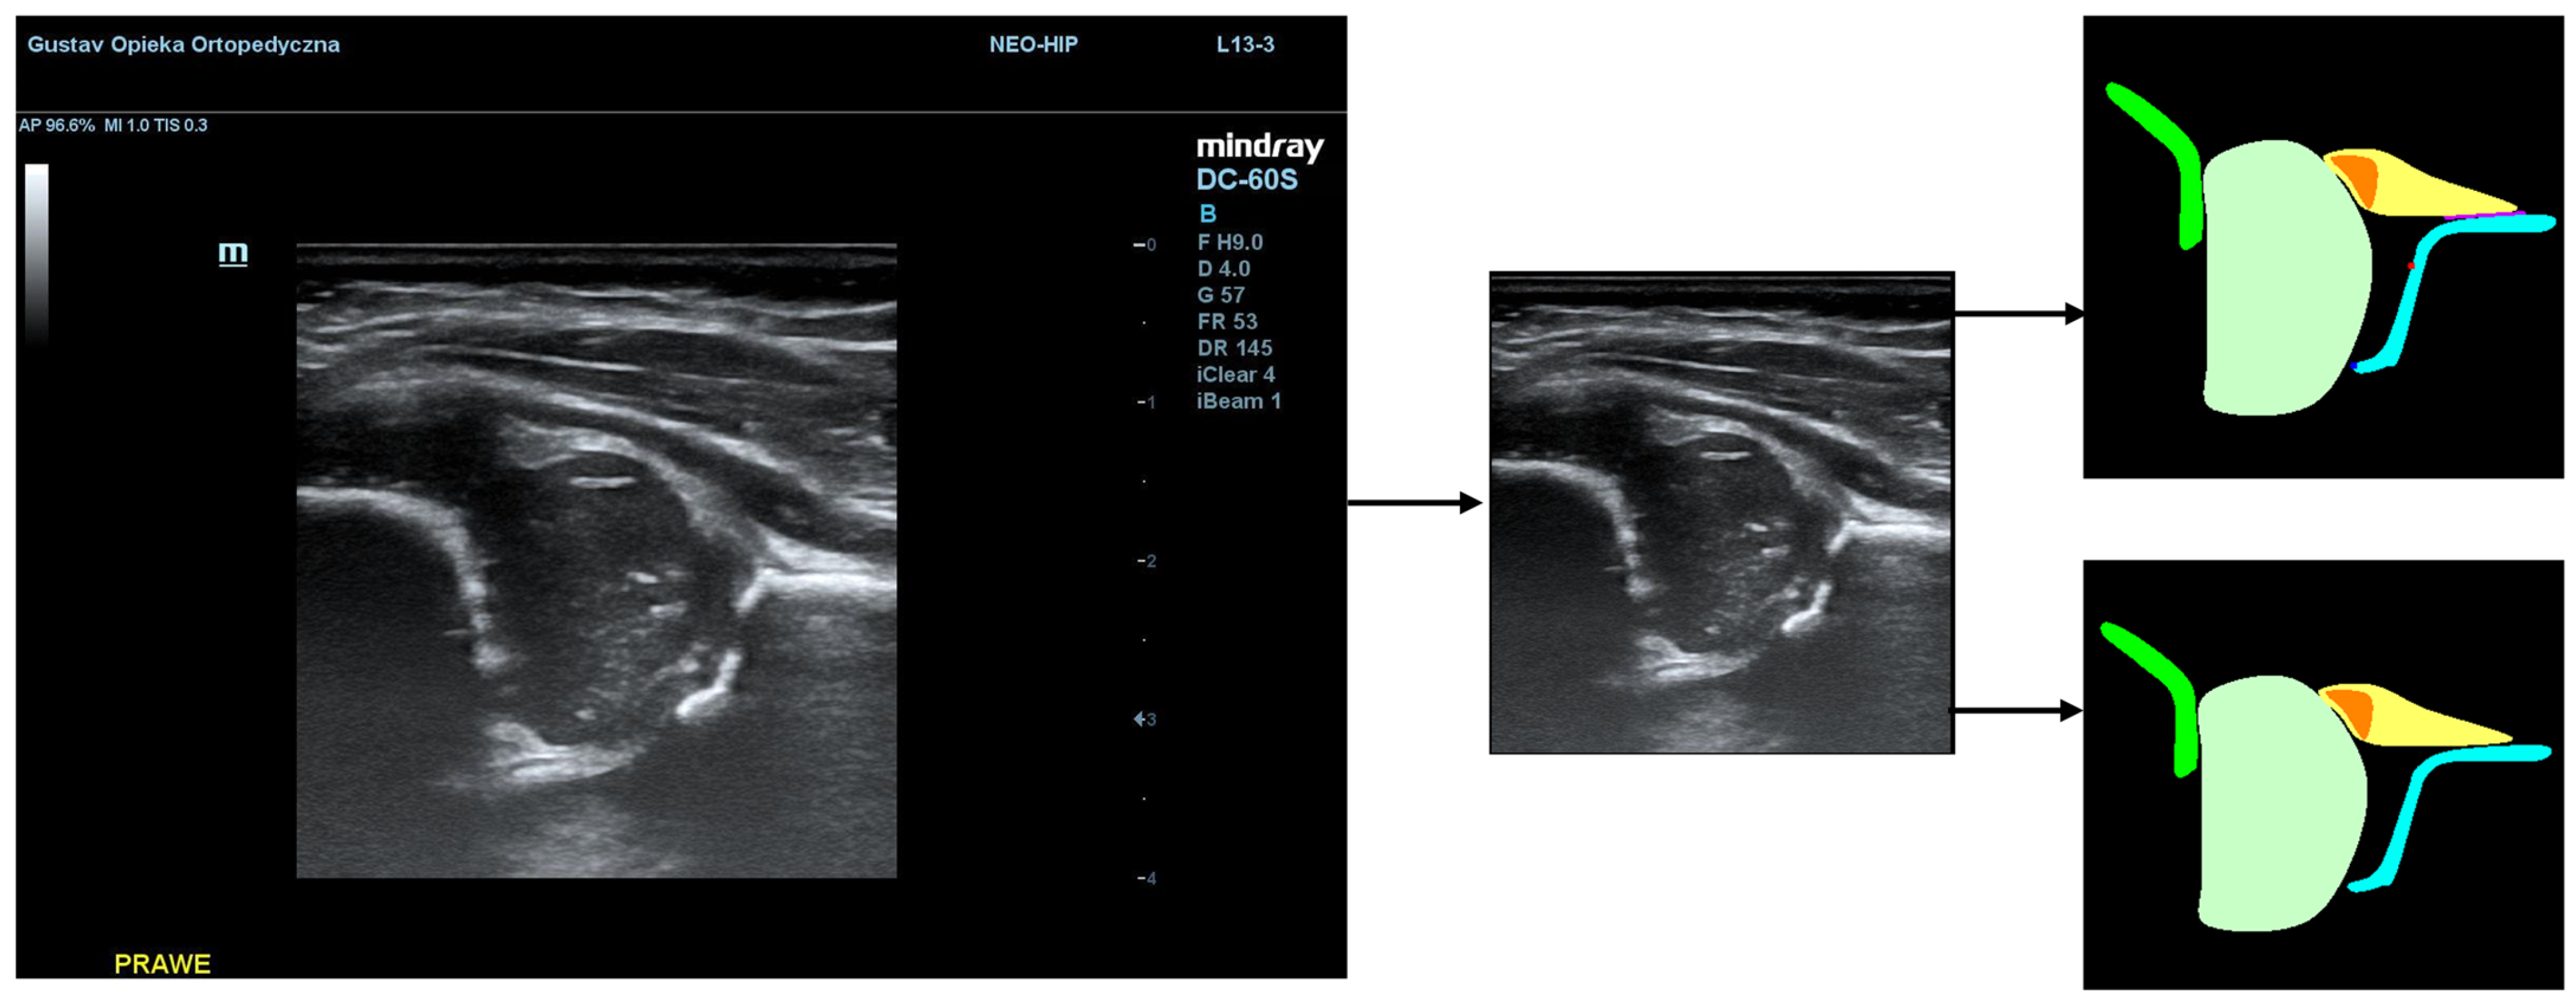

The structures were annotated by three independent orthopedic surgeons trained in the Graf method who had participated in a Graf-accredited course. The contours of the anatomical structures in the US images were marked using points along the edges of the target anatomy by dedicated software on selected frames. In the annotation process, a maximum of 25 frames from each video were selected by the reporting physician as the best. Annotating physicians selected structures for marking from a drop-down list among the objects on Checklists I and II according to Prof. Graf, necessary for the assessment of hip joints for DDH (Figure 1). Frames were selected for annotation only when it was possible to mark 5 or more objects. Furthermore, at least one selected frame in each video was classified as diagnostic, according to the Graf methodology (standard plane) [14].

Figure 1. Ultrasound image of the hip in Graf standard plane (a) and labeling of anatomical structures (b). The labeled diagram (b) includes 5 anatomical structures, i.e., chondro-osseous border (red-1), femoral head (purple-2), cartilaginous roof (yellow-3), bony roof (beige-4), and labrum (light purple-5). Other landmarks include lower limb (orange-6), bony rim (light blue-7), and baseline (pink-8).

Jcm 14 06332 g001